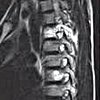

Удаление гематом спинного мозга

Удаление спинальных гематом. Хирургическое вмешательство, при котором выполняется эвакуация содержимого эпидуральной или субдуральной гематомы. Показаниями к операции являются прогрессирующие симптомы сдавления спинного мозга, которые возникают в течение периода от нескольких часов до нескольких недель после травмы, что проявляется в ухудшении чувствительности, движения и дисфункции органов малого таза. Декомпрессивная ламинэктомия с удалением гематомы из спинного мозга проводится после подтверждения диагноза дополнительными методами обследования. Прогноз обычно благоприятный, наилучший результат наблюдается при раннем устранении сдавления нервной ткани.